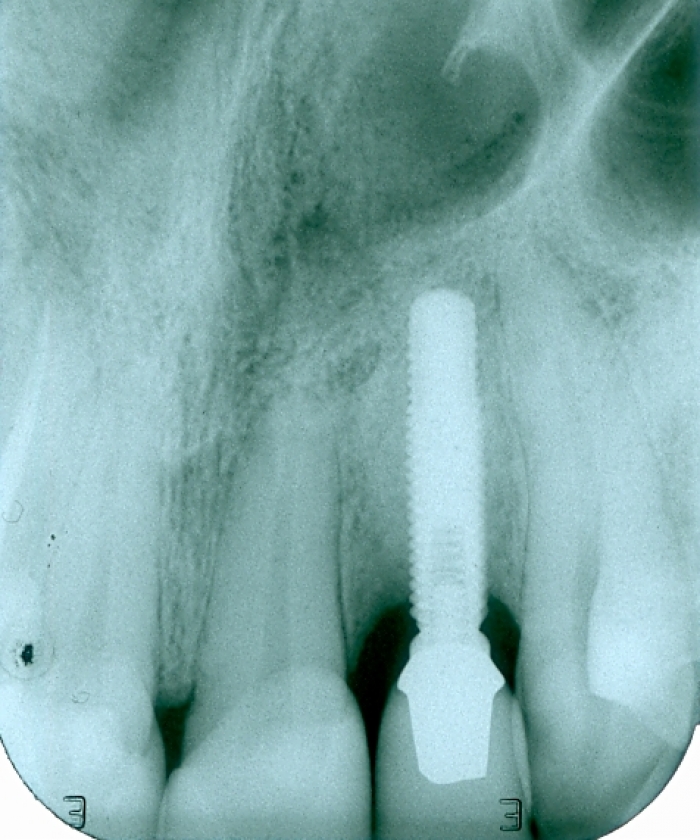

Raio X após troca da prótese fixa de porcelana